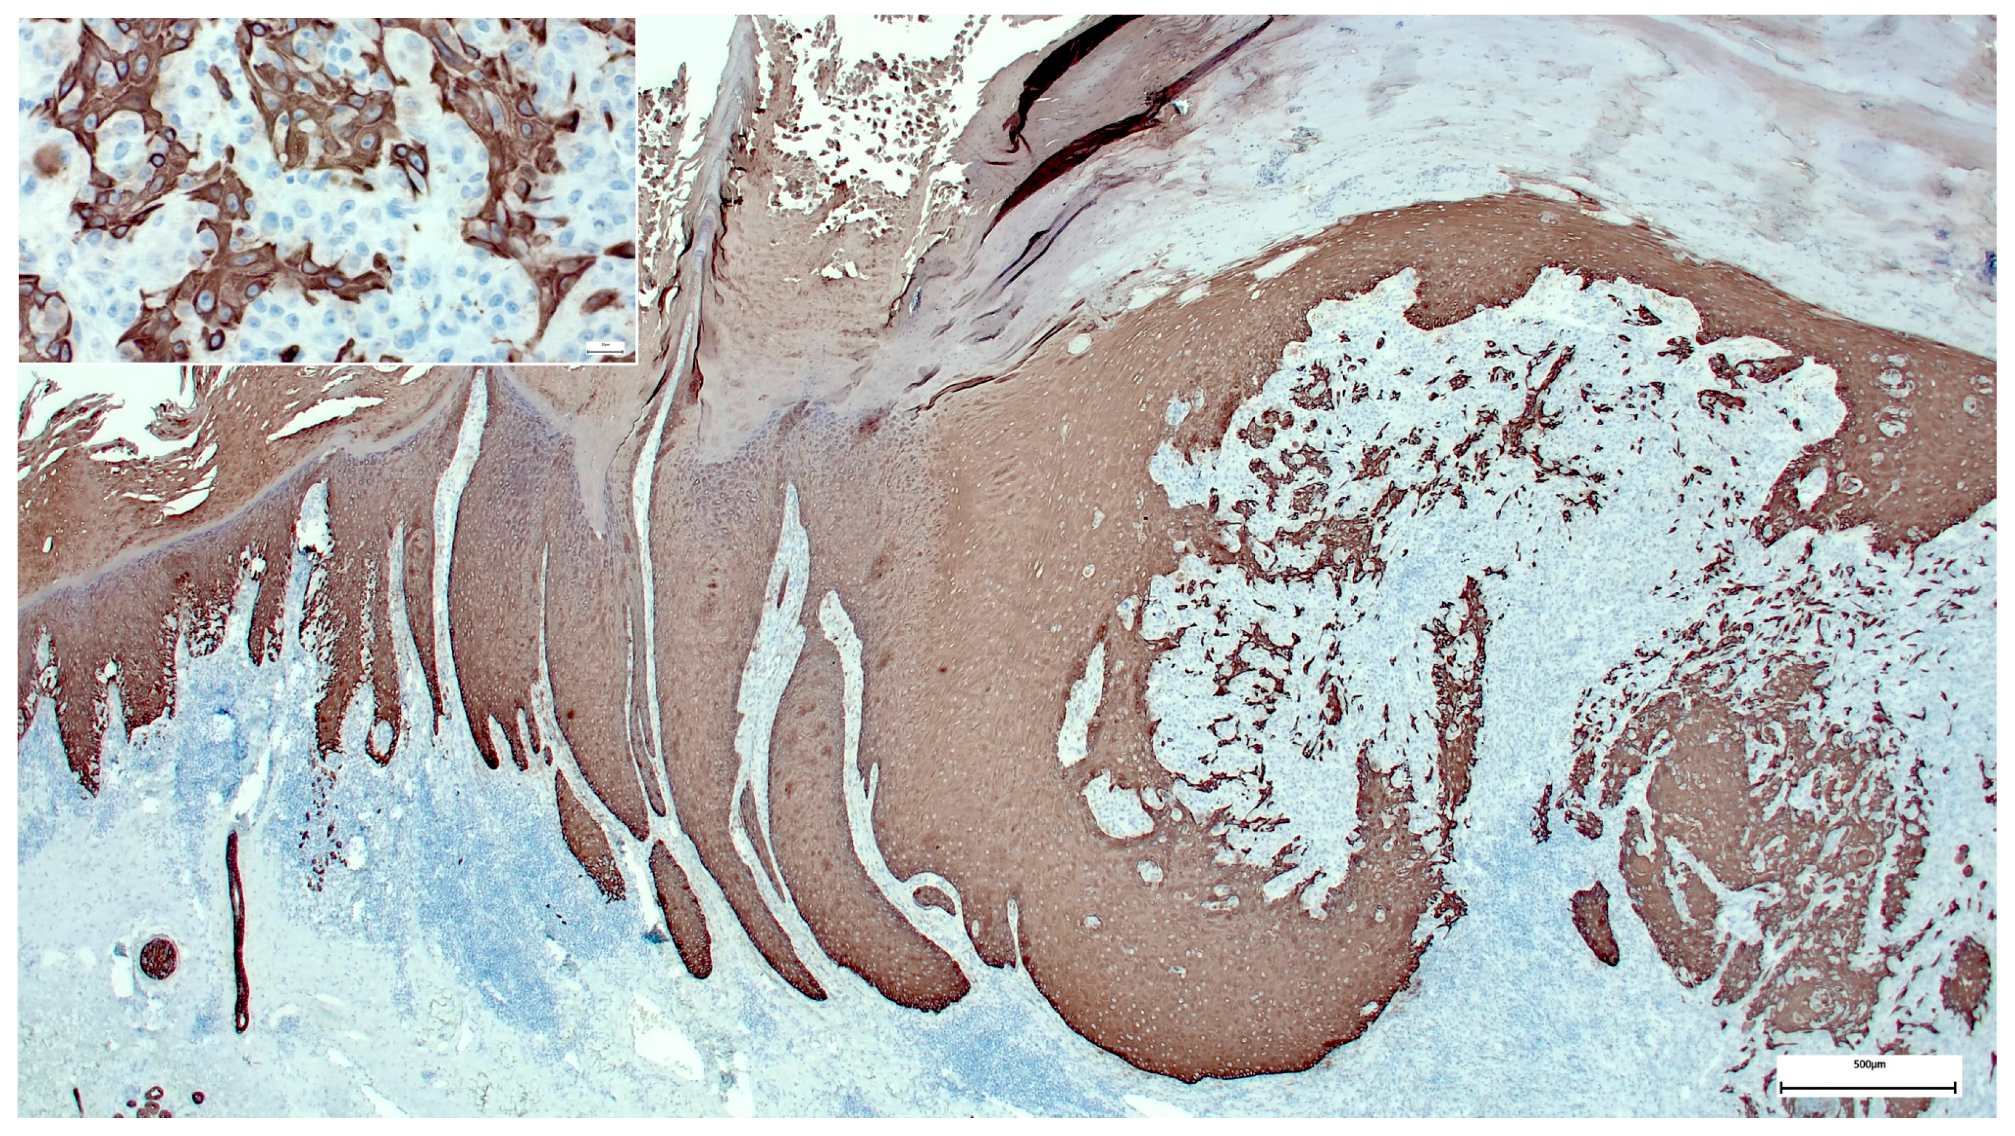

A Wolf in Sheep’s Clothing: Collision of Melanoma and Keratoacanthoma

:1. Case Presentation